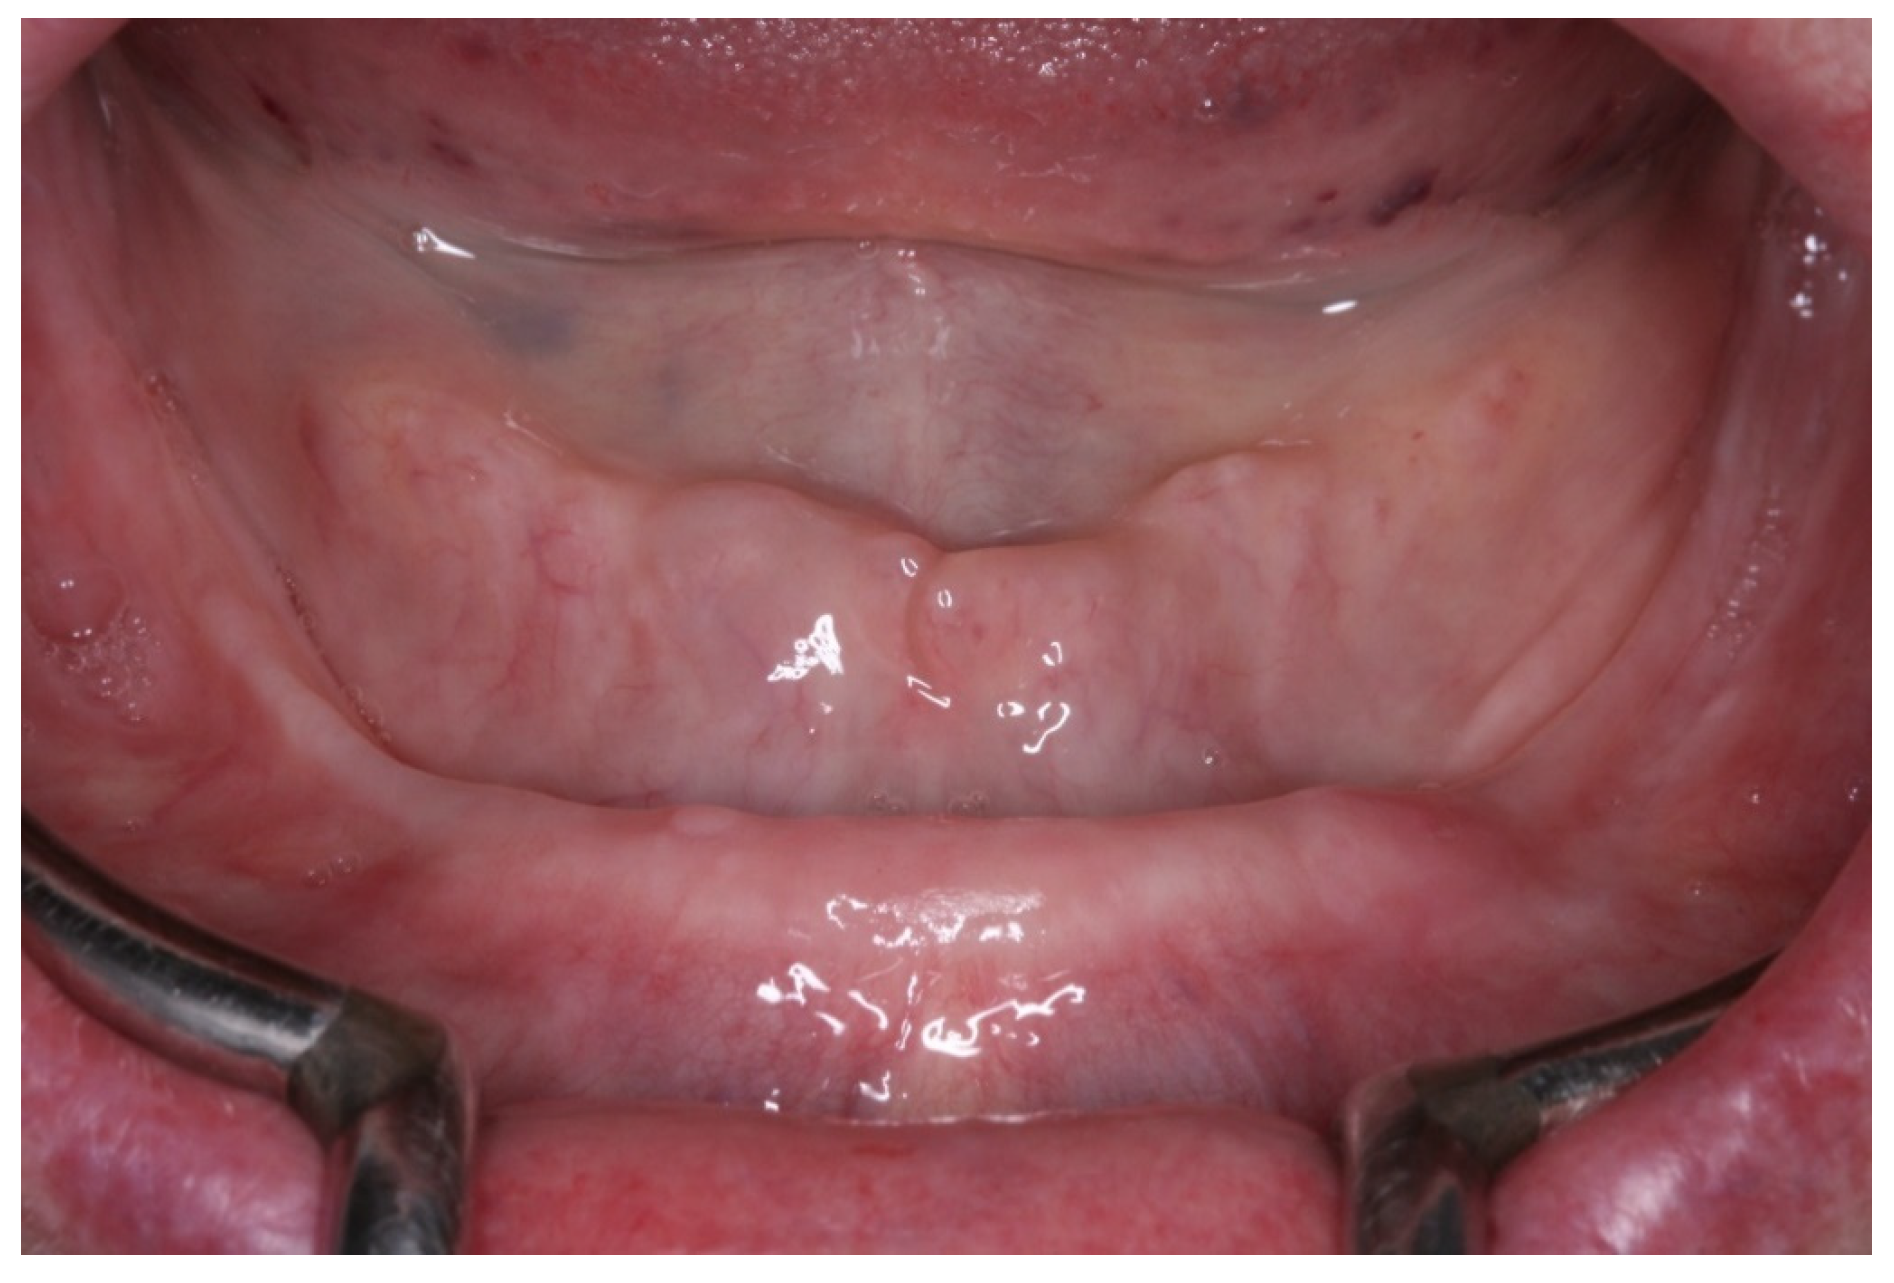

2. Case Report